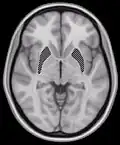

Horizontal slice of MRI-image showing the putamen. The other nuclei of the basal ganglia (caudate nucleus and globus pallidus) can be seen as well. -